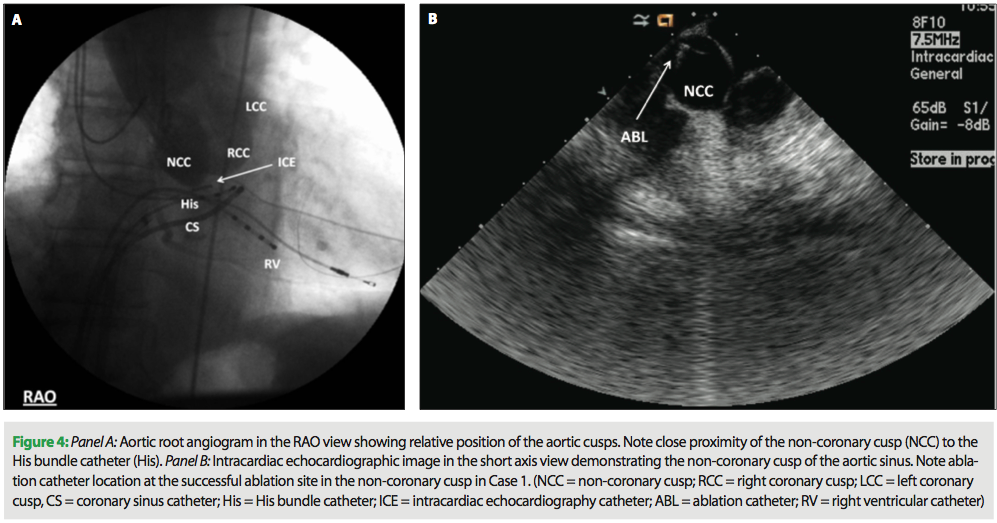

The ablation catheter was advanced to the aortic root under fluoroscopic and intracardiac echo guidance (Figure 4, Panels A and B). At this location, low amplitude, multicomponent atrial electrograms with activation times earlier than those in the His bundle region were noted (Figure 5, Panel A). Ablation at this location terminated SVT in 2.6 sec (Figure 5, Panel B). Ablation catheter location at the successful site in NCC is shown in Figure 6 (Panels A and B). Two 60-second applications were delivered at this location (30 W, 55° C), and AT was no longer inducible despite aggressive testing. Patient remained arrhythmia-free at one-month follow up. There were no complications.

Radiofrequency ablation in the NCC has been shown to be safe and effective when local atrial activation in the NCC precedes that of the para-Hisian region, and the surface p-wave by ≥20 ms.21 Caution should be exercised whenever radiofrequency energy is applied in the para-Hisian region due to its proximity to the native conduction system. Cryoablation has played a significant role in the arrhythmias of such high-risk situations such as the pediatric patient or slow pathway modification near the AV node.22-24 However, its use in para-Hisian AT has been limited, but seems promising.23,24 Careful multimodality imaging with aortic root angiography, intracardiac echocardiography, 3D-electroanatomic mapping (often coupled with MRI or CT) and fluoroscopy can help to identify and avoid the AV node and His bundle. Pacemapping can help separate the NCC from the right coronary cusp; NCC pacing will result in atrial capture, whereas right coronary cusp pacing results in ventricular capture due to proximity to the left ventricular myocardium. When mapping the NCC, intracardiac echocardiography can be a valuable tool to assess proper catheter positioning. An aortic root angiogram and/or coronary angiogram should be performed prior to ablation if there is concern about proximity of the arrhythmia focus to the coronary ostia.